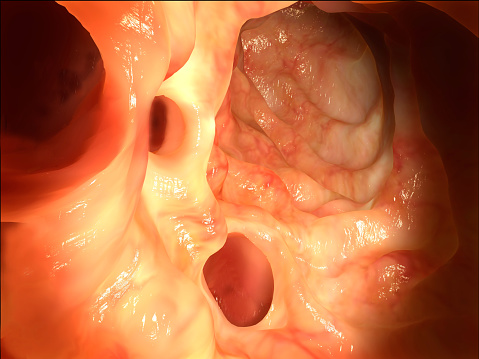

Colon polyp risk reduced 33 percent by legumes (beans) and 40 percent by brown rice in the diet: Study

Colon polyp risk reduced 33 percent by legumes (beans) and 40 percent by brown rice incorporated into one’s diet. The study found eating legumes at least three times a week and brown rice at least once a week was linked to a reduction in colon polyps. Lead author Yessenia Tantamango said, “Eating these foods is ...click here to read more